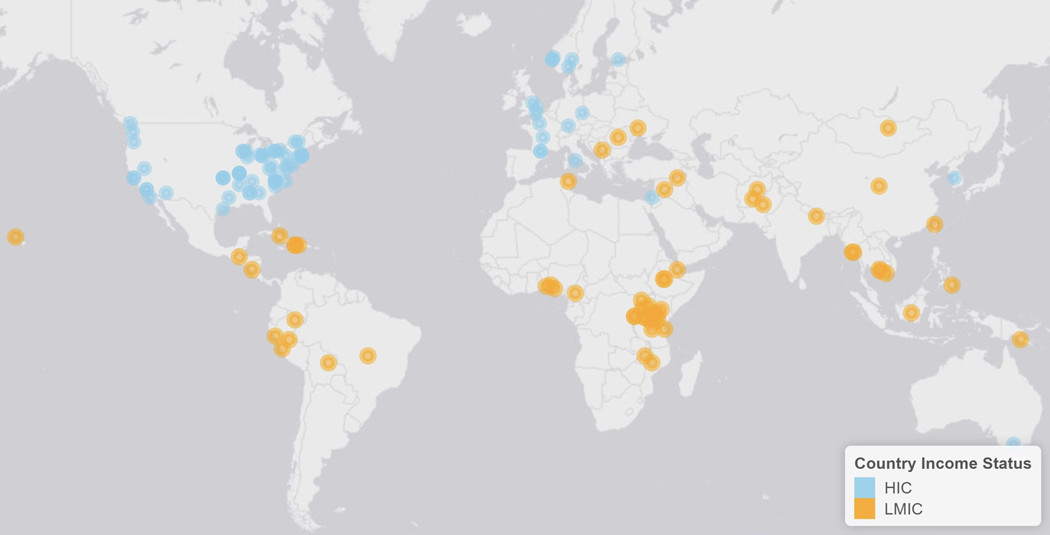

当今世界,低收入和中等收入国家(LMICs)尚未从神经外科技术的发展中受益。在这些LMICs国家中,大多数国家神经外科的处理能力很小甚至没有。在该文中,作者广泛地研究了全球从事神经外科领域的个人、组织和大学等不同层面应对许多LMICs国家所面临的挑战时所采取的不同方式。关键策略包括外科训练营、教育计划、培训计划、卫生系统加强工程、卫生政策变更/发展和宣传。全球神经外科已经开始联合起来,向前迈出了一大步,为这项工作统一发声。多边、多国参与的大规模合作将是我们面临全球神经外科领域中的问题时采用的唯一有效的解决方案。关键的参与者已经开始致力于实现这一最终解决方案,我们坚信全球神经外科的未来一片光明。(译者注:全球神经外科发展的不均衡,如何促进全球神经外科医生的同质化,这也是2019年WFNS特别会议的主题之一)。

图:全球神经外科项目分布(蓝色代表高收入国家,橙色代表低收入和中等收入国家)。